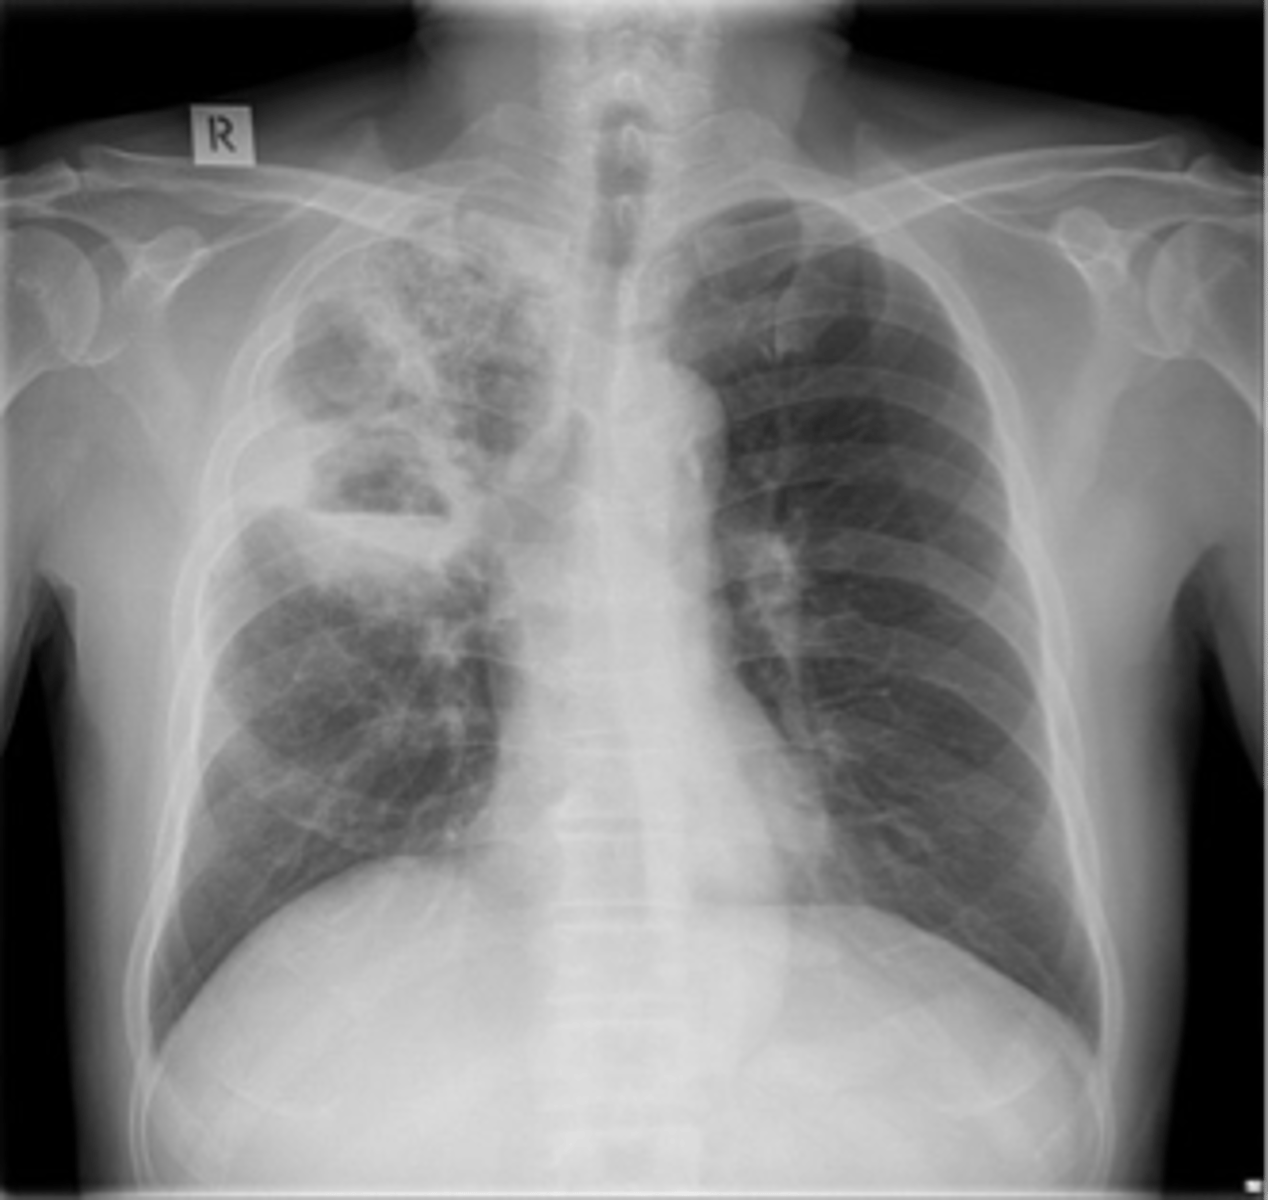

Lung cancer- squamous cell carcinoma

squamous cell carcinoma